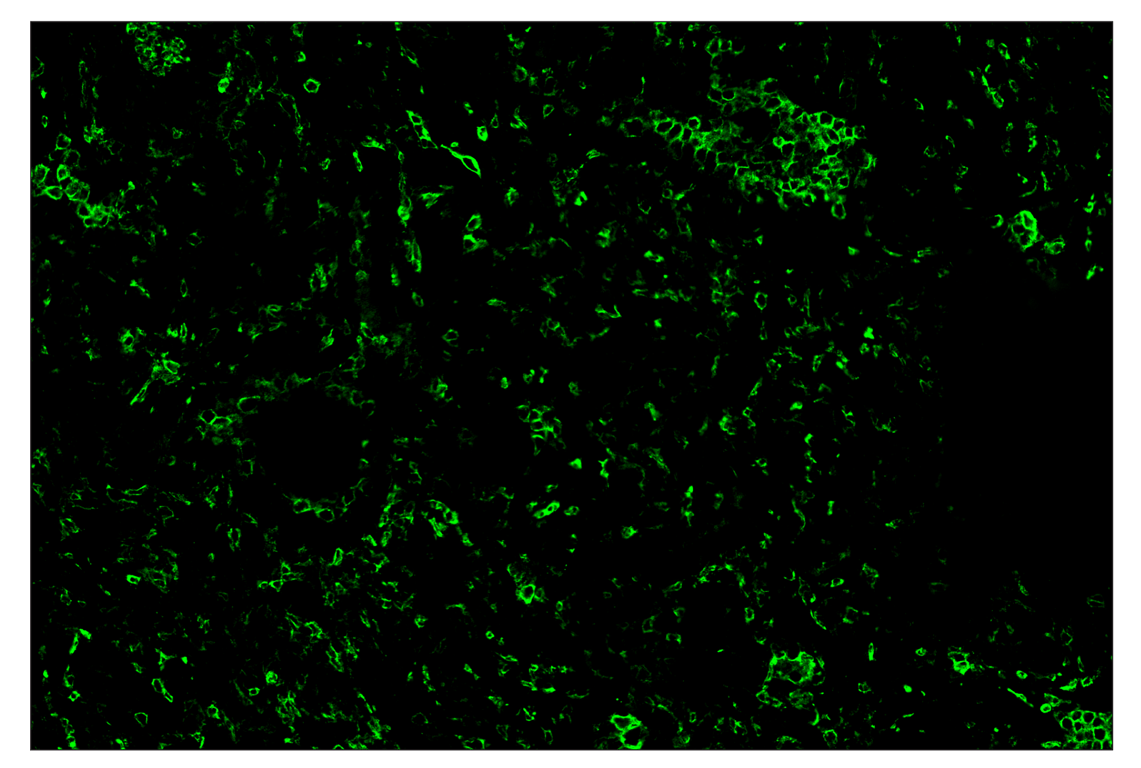

SignalStar™ immunohistochemical analysis of paraffin-embedded human non-small cell lung carcinoma using CD11b/ITGAM (D6X1N) & CO-0037-488 SignalStar™ Oligo-Antibody Pair #19619 (green). All fluorophores have been assigned a pseudocolor, as indicated. Staining was performed on the BOND RX autostainer by Leica Biosystems.

Immunohistochemistry Image 2: CD11b/ITGAM (D6X1N) & CO-0037-647 SignalStar<sup>™</sup> Oligo-Antibody Pair